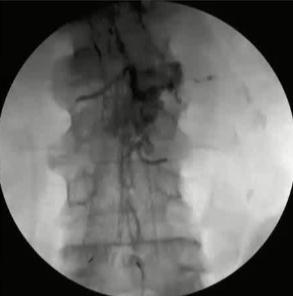

栓塞材料的可及性(例如病灶栓塞材料的可到达性)accessability (e.g. reachability of the nidus) 栓塞的预期深度intended deepness of embolization 如果需要让栓塞填满最后1mm 预期效果(例如:门静脉栓塞的炎症)intended effect (e.g. inflammation in PVE) 凝血状态(达到止血效果所需的时间)coagulation state (duration until hemostasis) 并发症(过敏、心律不齐、肺动脉高压、肝纤维化等)comorbidities (allergies, arrythmia, pulmonary hypertension, lung fibrosis etc.) 处于危险中的结构(包括下游部分-downstream和反流部分) structures at risk (downstream & backwash) 靶病变定位(浅层与深层) target lesion localization (superficial vs. deep) 不会选择一些会引起炎症的东西,因为那会病人来说真的很痛苦浅层病变 栓塞所需的速度(例如:危及生命的出血情况)required speed of embolization (e.g. life threatening hemorraghe) 院外专业人员(DSA技术人员和介入放射科医生)local expertise (technicians & IR's) 可用性与定价 availabilty & pricing Patient assessment for the choice of the ideal liquid emboli 影像学 62岁 男性

腹腔侧支循环